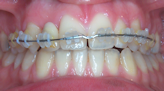

Les appareils fixes (appareils multiattaches communément appelés bagues) que le patient ne peut pas retirer. Ils sont constitués de boîtiers ou verrous collés ou scellés sur les dents, reliés par des fils métalliques dont l’alliage, la section, la forme sont déterminés par les différentes étapes du traitement. Ils peuvent être collées en externe ou en interne.

les attaches ou boitiers métalliques externes,

les attaches ou boitiers esthétiques en céramiques (moins visibles) externes